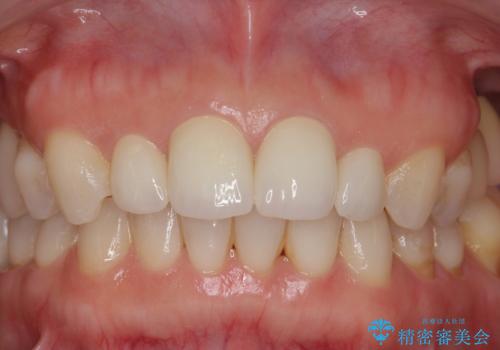

隣の前歯が小さいため、4本被せてバランスをとりました。

4本セラミックにすると大きさだけでなく、色も揃えられるのでおすすめです。

- ジルコニアクラウン(スタンダード) 11万円×4本、仮歯 1万円×4本費用は治療当時の料金となります

歯の向きは悪くなかったため、神経は取らずに治療しました。